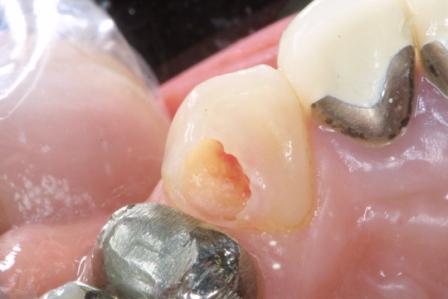

表題画像はC3と呼ばれる神経に虫歯が達して痛みが出ている状態です。

今ではこのような状況でも神経を取らないで済むようになっていますが、

実験室レベルではこのような深い虫歯を発生させることはできていません。

このタイプの虫歯はよく見かける症例で、